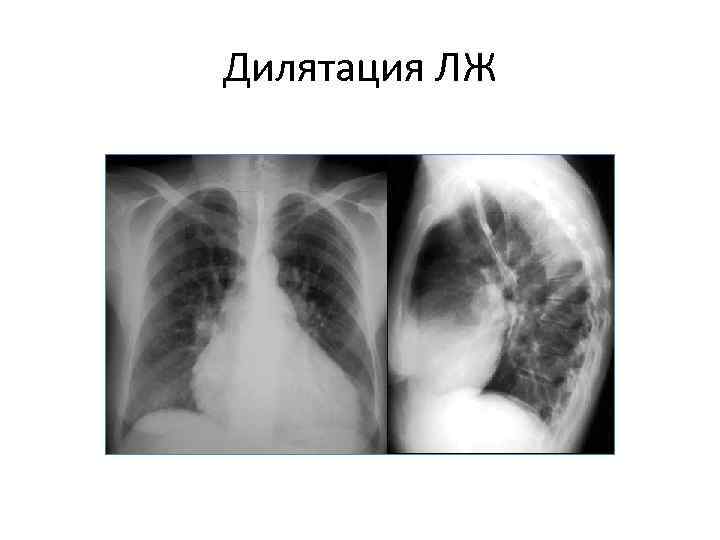

Причина увеличения ЛЖ • Для разграничения гипертрофии и дилятации левого желудочка, по аналогии с левым предсердием, оценивают степень и характер выбухания его дуги. • Пологая дуга - дилятация, закругленная – гипертрофия. • Бывают сочетания, сказать что преобладает - трудно.

Дилятация ЛЖ

Различить гипертрофию и дилатацию обычно несложно: • Гипертрофия дает закругление дуги (в данном случае левого желудочка) • Для дилатации характерна удлиненная пологая дуга • Это же правило характерно и для других полостей сердца

Дилатация полостей • Дилатация - это расширение любой полости сердца, как правило, с истончением стенок. Состояние развивается вследствие частичного возвращения крови в момент диастолы (расслабления сердца), через плохо смыкающийся клапан, назад в полость. Степень дилатации отражает как объем регургитации, так и резервные возможности сердечной мышцы.